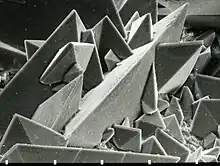

Types

La nature de ces calculs est très variable et reflète les mécanismes à l'œuvre dans leur formation[24]. Selon la classification de Daudon, on distingue 7 grands types de calculs définis selon leur composition cristalline. Ces différents types ne sont pas exclusifs l'un de l'autre au sein d'un même calcul : en effet, si certains calculs ne sont constitués que d'un seul type et sont donc dits "purs", la plupart sont un mélange de plusieurs types et sont donc dits "mixtes". Ces 7 types sont les suivants :

- type I : oxalate de calcium monohydraté, également appelé whewellite

- type II : oxalate de calcium dihydraté, également appelé weddellite

Les calculs oxalocalciques (types I et II) sont de loin les plus fréquents à l'heure actuelle dans les pays à mode de vie occidental, représentant environ 80 % du total. Ils sont dans 9 cas sur 10 dus à des erreurs alimentaires, et dans 1 cas sur 10 secondaires à une maladie sous-jacente. Quelle que soit la cause (erreurs alimentaire ou maladie sous-jacente), il en résulte un excès d'oxalate et/ou de calcium dans les urines. Lorsque l'excès urinaire porte préférentiellement sur l'oxalate, ce sont des calculs de whewellite (type I) qui se forment. Lorsque à l'inverse l'excès urinaire porte surtout sur le calcium, ce sont des calculs de weddellite (type II) qui se forment.